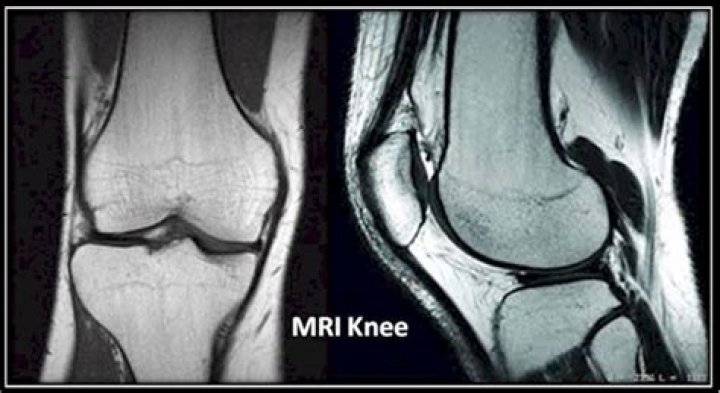

Knee MRI. Magnetic resonance imaging (MRI) of the knee uses a powerful magnetic field, radio waves and a computer to produce detailed pictures of the structures within the knee joint. It is typically used to help diagnose or evaluate pain, weakness, swelling or bleeding in and around the joint.

Will an MRI show a torn meniscus?

MRI gives a good picture of the size of a meniscus tear and where it is. It also shows ligaments, cartilage, and tendons. MRIs of the knee are helpful to identify a meniscus tear and to find any related injuries to the ligament, cartilage, and tendons.

Will an MRI show arthritis in the knee?

MRI is the most effective way to diagnose problems within any joint and the image sensitivity makes it the most accurate imaging tool available in detecting arthritis and other inflammatory changes.